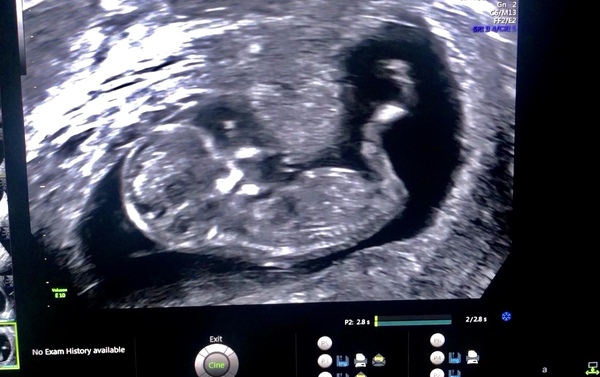

Nilonilo · 30/03/2023 23:44

Ladies!!! 12 week scan is here. I have a son and a daughter but just wondering what this one may be? Boy or girl?😍

Skull theory